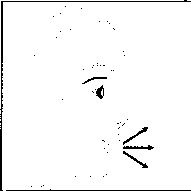

- Ağızlığı ağzınıza yerleştiriniz ve başınızı hafifçe geriye doğru eğiniz.

- Dudaklarınızla ağızlığın etrafım sıkıca sarınız.

- Hızlı, duraksamadan ve alabildiğiniz kadar derin bir nefes alınız.

7. İlacı derin bir şekilde hava yollarınıza çekmek

için:

Not: Kapsülün, kapsül bölmesinin üzerindeki alanda dönmesine bağlı olarak bir vızıldama sesi

duymalısınız. Eğer bu vızıldama sesini duymazsanız, kapsül bölmesini açınız ve kapsülün, kapsül bölmesinde sıkışıp sıkışmadığını kontrol ediniz. Daha sonra 7. basamağı tekrarlayınız. Kapsülü sıkıştığı yerden kurtarmak için düğmelere tekrar BASMAYINIZ.